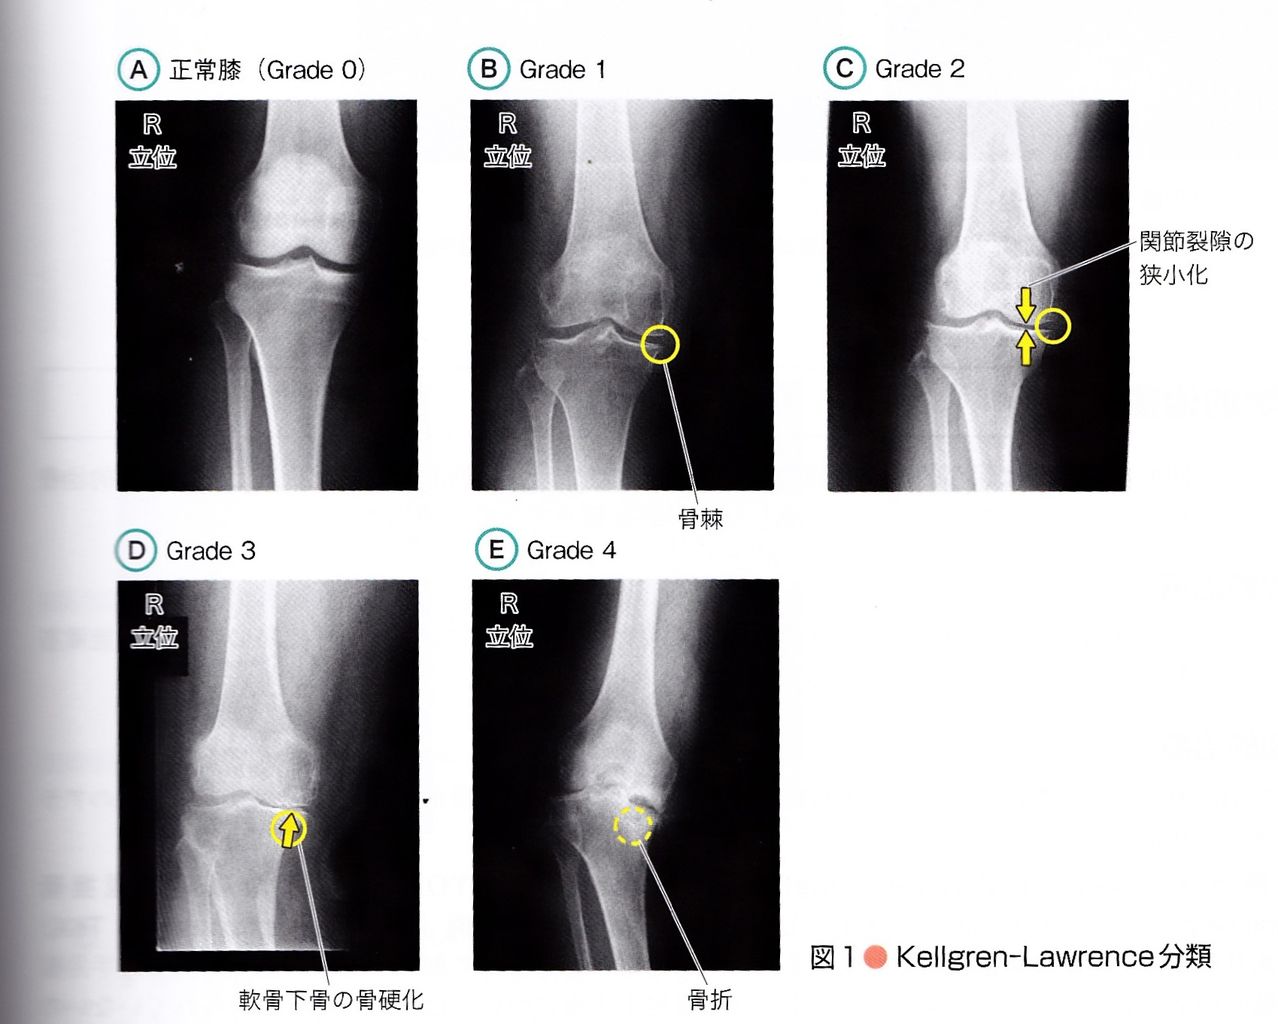

変形性膝関節症 による痛み監修: 島根大学医学部 整形外科学教室教授 内尾 祐司 先生監修: 島根大学医学部 整形外科学教室教授 内尾 祐司 先生. Using apkpure app to upgrade 変形性ひざ関節症説明ツール, fast, free and save your internet data. 436 likes · 24 talking about this.